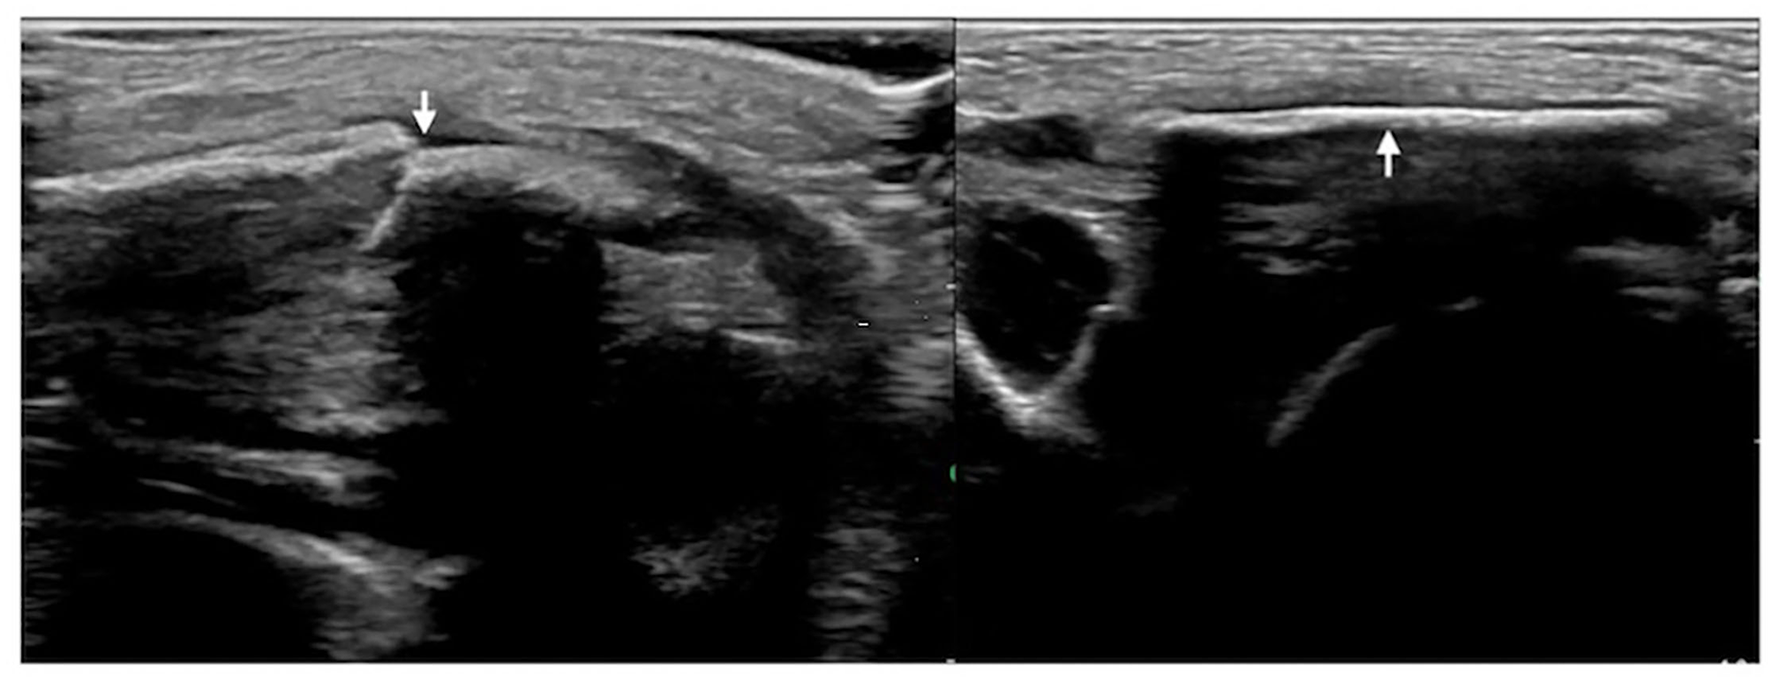

Figure 3

Left clavicle fracture. The infant was G4P2 with a gestational age of 41 weeks, forceps delivery, and a birth weight of 3,670 g. The patient was admitted to the hospital 41 h after birth due to jaundice for 6 h. Physical examination revealed asymmetrical clavicles as well as local swelling and bone rubbing on the left side. Ultrasound showed interrupted cortical continuity, broken end formation, and dislocation in the left midclavicular segment (left); the right clavicular continuity was intact, and the cortical bone was smooth.

Figure 4

Humeral fracture. The infant was G2P1 with a gestational age of 39+2 weeks, forceps delivery, and birth weight of 4,000 g. The patient was admitted to the hospital 20 h after birth due to a 6-h fever. The diagnosis was intrauterine pneumonia. Physical examination revealed swelling, tenderness, limited mobility, and loss of the primitive reflex of the right upper limb; thus, the fracture was suspected. Ultrasound showed interrupted cortical continuity, visible broken ends, displacement, separation, and angulation of the right humerus.